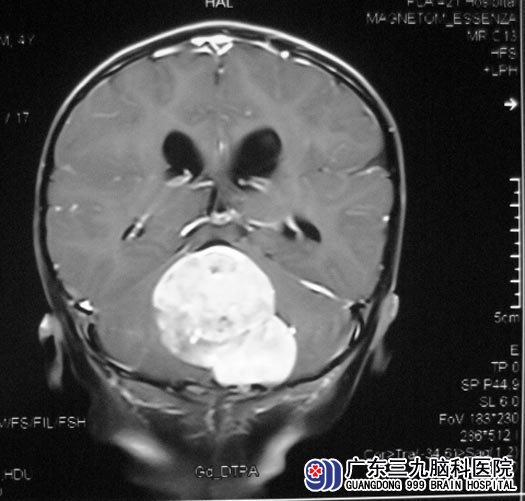

一月前,小宇出现走路不稳,步履蹒跚,易摔倒,家人以为又一次患上手足口病,立即去医院就诊。医生建议行头颅MR检查,结果示;“四脑室占位,大小约4.5cm×4.5cm×5.0cm”,医生告诉他们,手术难度非常大。 http://www.999brain.com/

广东三九脑科医院综合神经外科 鲁明主任了解病史及查阅影像资料后,考虑为髓母细胞瘤合并有梗阻性脑积水。

5月8日,鲁明主任主刀,在全麻下行四脑室内肿瘤切除术。先打开枕大池,释放脑脊液后压力下降,结扎枕窦,见左侧小脑上蚓部肿瘤,呈粉红色,质地不均匀,血供丰富,边界清楚。肿瘤与脑干粘连较重,沿肿瘤与延髓交界处向上分离,行瘤内部分切除,减小肿瘤体积,向上切除部分肿瘤后暴露四脑室顶部,见脑脊液流出,明胶海绵保护。向脑干处继续分离切除肿瘤,见肿瘤与四脑室底部边界清楚,予以仔细分离切除;显微镜下予肿瘤全切,四脑室完整暴露,创面反复止血满意,可见中脑导水管开口,脑脊液引流通畅。手术顺利,术后CT复查,小宇没有出现脑积水等术后并发症。现已康复出院。术后病理证实为:(四脑室)髓母细胞瘤(WHO IV级),后期还需要接受进一步的放化疗。